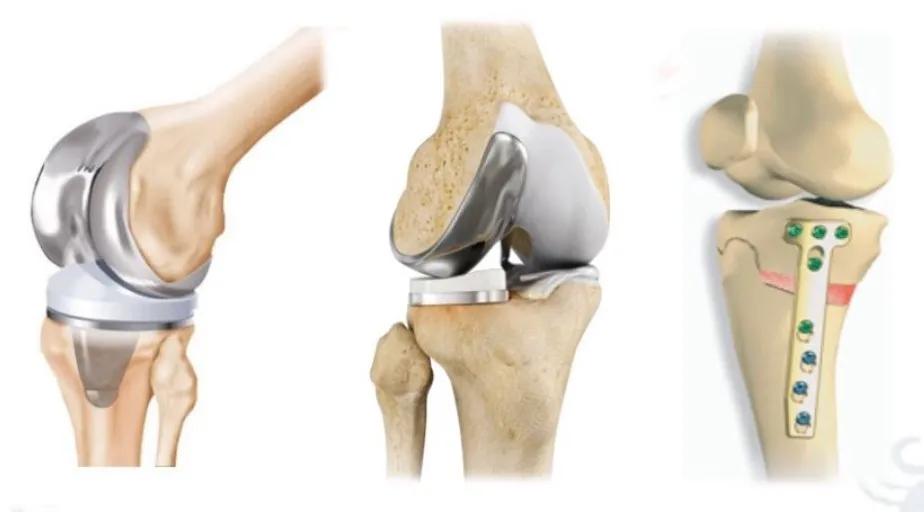

该患者年纪相对较轻,日常活动量大,膝关节活动度接近正常,胫骨内翻大于5°,胫骨近端内侧角小于85°,膝关节外侧间室功能正常。因此,本病例选择胫骨近端高位截骨术(High Tibial Osteotomy, HTO)治疗,术中采用胫骨近端内侧开放楔形截骨,按术前设计撑开10mm楔形间隙,纠正术前内翻畸形,同时矫枉过正减轻内侧间室压力。术后双下肢全长负重位X线片示右下肢力线通过胫骨平台外侧髁间棘。

该患者年纪较长,膝关节活动轻度受限,胫骨内翻小于5°,胫骨近端内侧角正常,膝关节内翻为关节内软骨磨损所致,且可以通过外翻应力完全纠正,膝关节外侧间室功能正常。因此,本病例选择内侧单髁膝关节成形术(Unicompartmental Knee Arthroplasty, UKA)治疗,手术选择活动平台假体,恢复内侧副韧带长度和张力,纠正关节内翻畸形。术后双下肢全长负重位X线片示右下肢力线通过膝关节中心。

该患者病史较长,呈典型全关节骨关节炎表现,伴固定屈曲内翻畸形。患者身体一般状况良好,本人及家属均有缓解疼痛、纠正畸形、提高生活质量的愿望。因此,本病例选择全膝关节表面置换术(Total Knee Arthroplasty, TKA)治疗,手术选择后稳定型假体,清理骨赘和炎性滑膜,恢复关节面的友好关系,重建双下肢正常力线。术后双下肢全长负重位X线片示双下肢力线通过膝关节中心。